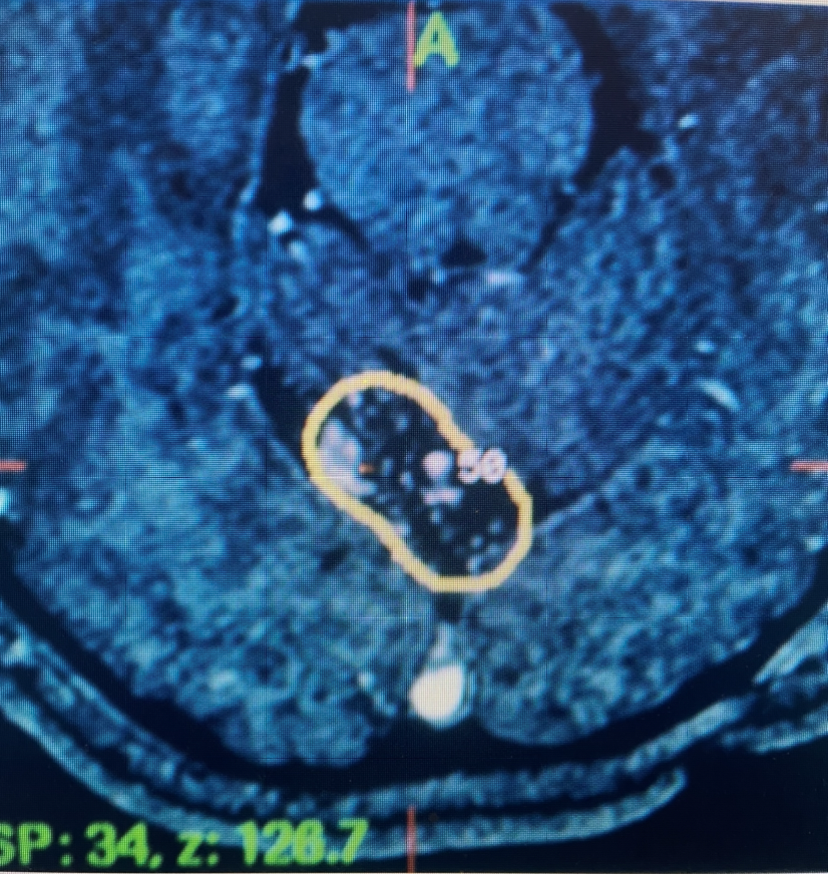

She returned for a follow up visit 19 years after the Gamma Knife treatment just to check up on things. She felt well and was neurologically intact. MRI and CTA of the brain were performed, which demonstrated complete obliteration of the AVM.

Figure 2A. Axial MRI with contrast.